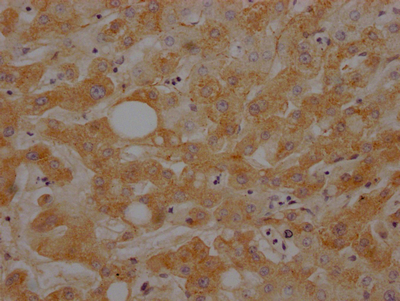

| C3 | C3 Recombinant Monoclonal Antibody | Human | ELISA, WB, IHC, FC | CSB-RA303909A0HU |

| C3 | C3 Recombinant Monoclonal Antibody | Human | ELISA, IHC | CSB-RA699863A0HU |